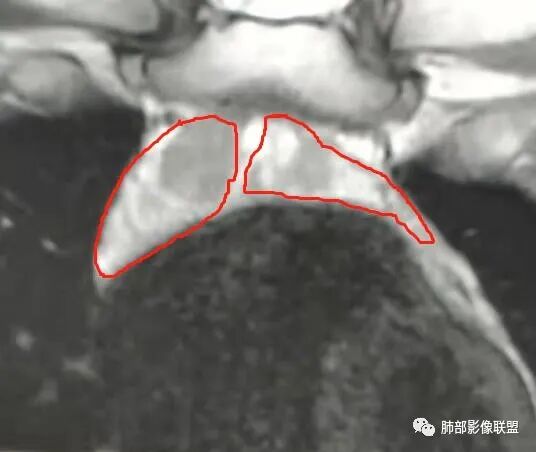

胸腺增生pk淋巴瘤,16 男,发病年龄两个都符合。支持胸腺增生证据 :

1 结节基本按左右叶分布,没有明显横跨中线的结节

2 结节形态基本类肾型,低张力状态?

3 结节周围有密度稍高的胸腺背景(区别于淋巴瘤) 磁共振正反相位估计有帮助

支持淋巴瘤证据:  左侧有结节凸于胸腺形态外,有无价值,待验证  综合  胸腺增生可能大

按分叶一边一个

是分叶还是两个病灶?

两个

两部分